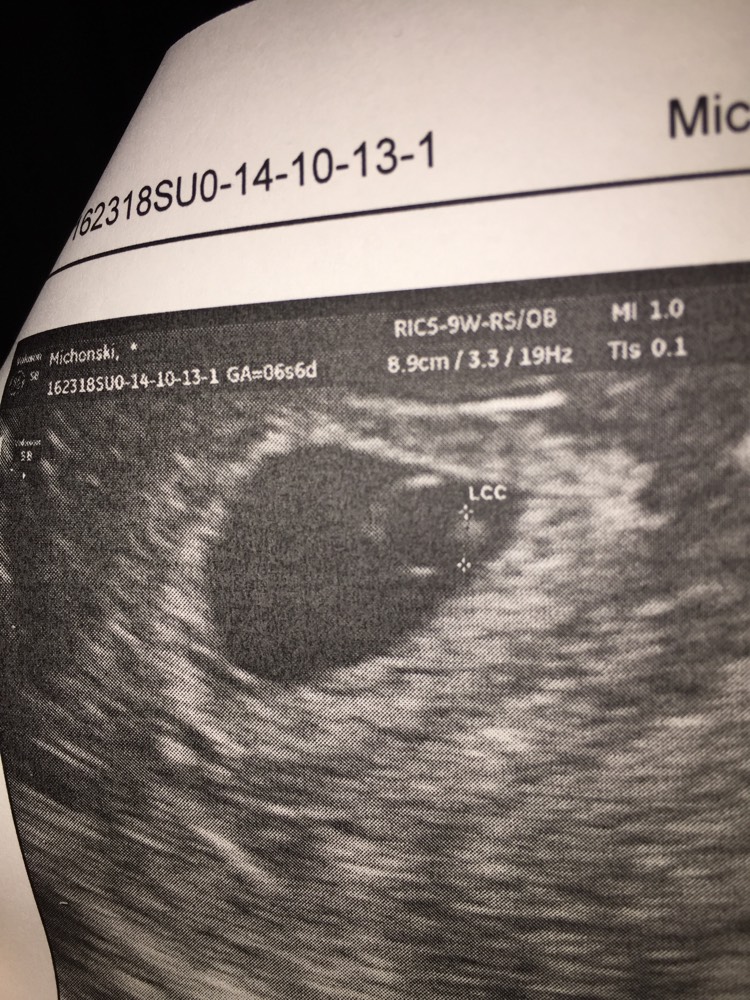

Trois échographies de dépistage sont recommandées aux femmes enceintes à chaque trimestre de la grossesse. Dans le cas d’une grossesse intra utérine d’évolution incertaine (sac gestationnel intra-utérin < 25 mm) sans vésicule vitelline visible, l’absence d’apparition d’un embryon avec une activité cardiaque à l’échographie endovaginale dans un délai d’au moins 14 jours permet d’affirmer que la grossesse est arrêtée (Grade C). Il mesure alors 2 à 3 mm.L'utilisation de la voie endovaginale est souvent nécessaire pour le voir.

De grossesse intra-utérine d’évolutivité incertaine, un contrôle échographique réalisé à plus de 7 ou 14 jours en fonction de la présence ou non d’une vésicule vitelline ou d’un embryon à l’échographie endovaginale permet d’affirmer l’arrêt de la grossesse (NP4). Une semaine plus tard a 5SA + 4 jours angoissée déprimée j’y retourne les taux est passer de 4000 à 00 puis de 00 à puis de à. Grossesse Définition du terme Grossesse non évolutive :.

Signes d'une grossesse non évolutive au troisième trimestre. De grossesse intra-utérine d'évolutivité incertaine, un contrôle échographique réalisé à plus de 7 ou 14 jours en fonction de la présence ou non d'une vésicule vitelline ou d'un embryon à l'échographie endovaginale permet d'affirmer l'arrêt de la grossesse (NP4). Les cas de grossesse non développée au troisième trimestre surviennent moins fréquemment qu'à un âge gestationnel plus précoce.